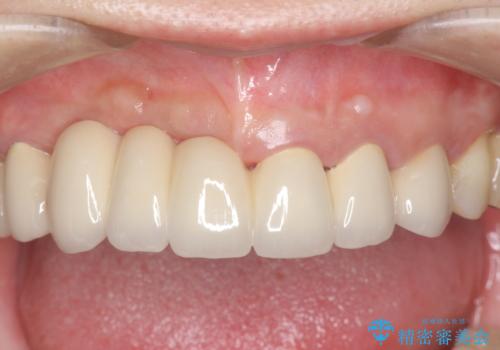

- 90万円 (仮歯×9 メタルボンドクラウン×9)費用は治療当時の料金となります

ブリッジは欠損した部位に臨在する歯を削り、被せなければいけないというデメリットがありますが反面噛む力が強い場合連結することで強大な咬合力に対抗できるというメリットも存在します。